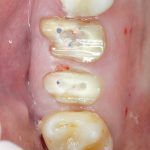

Возвращаемся к основной операционной области. Еще раз посмотрим на альвеолярный гребень, поофигеваем от его ширины и моих грандиозных планов:

На этом месте мне следует дать некоторые пояснения.

Я зафиксировал костный блок практически без адаптации на несколько винтов. Обрати внимание, что винты находятся в зоне, где не планируется установка имплантатов. Фиксация должна быть надежной, поскольку мне еще предстояла подготовка лунок для имплантатов. Трех винтов для этого вполне достаточно.

Дальнейшая адаптация костного блока свелась к сглаживанию острых краев. После чего я приступил к подготовке лунок и установке имплантатов.